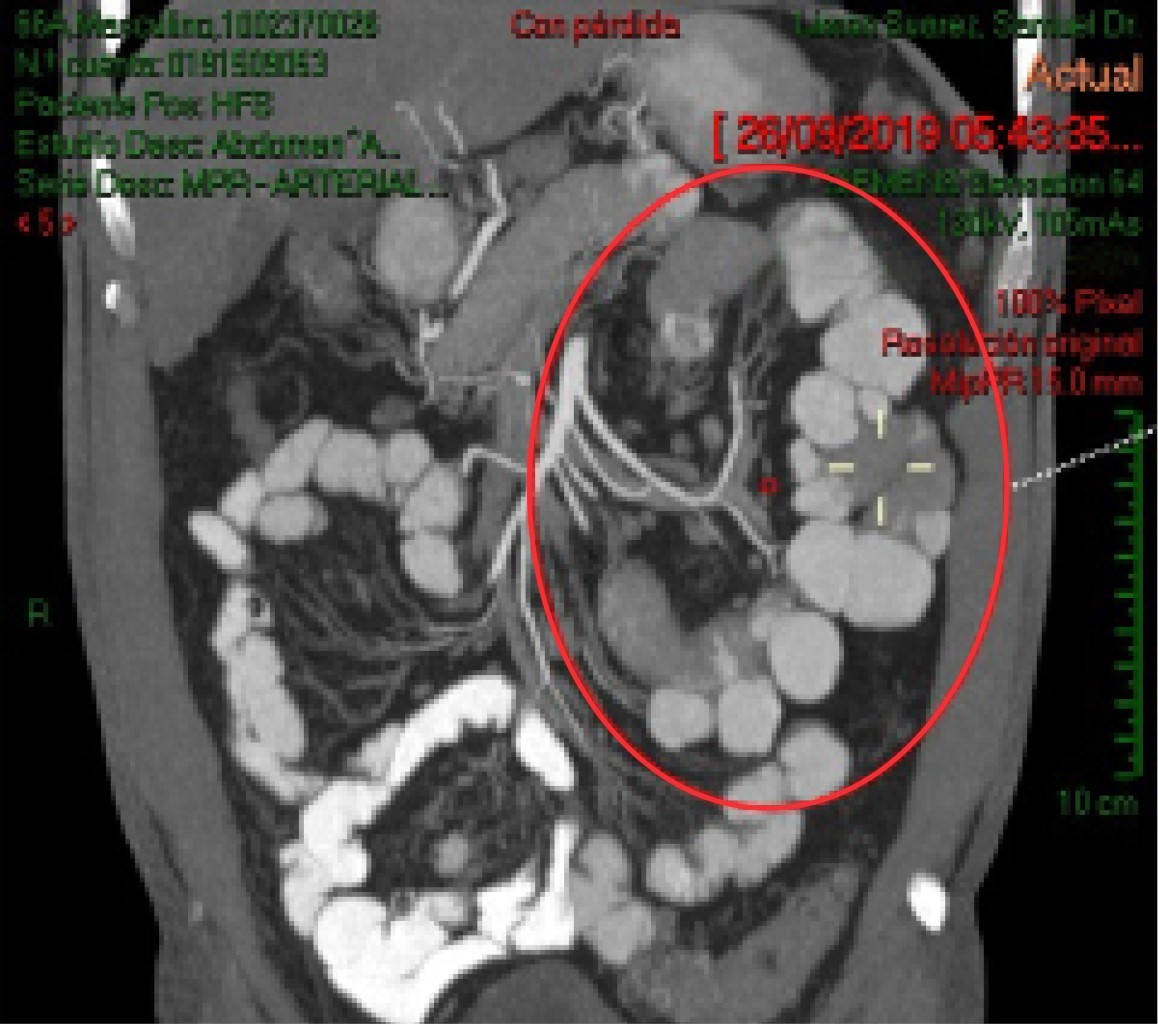

Jejunal diverticulitis with asymptomatic pneumoperitoneum. Non-operative management considerations

Introduction: Jejunal diverticula are saculations located on the mesenteric edge of the jejunum whose incidence is 0.2 to 4%. Pneumoperitoneum frequently translates acute surgical abdomen but can occur in pathologies that do not require surgical exploration. Objective: To recognize this pathology as an infrequent cause of chronic abdominal pain or acute surgical abdomen. Establish recommendations for its management. Clinical case: 66 years old male with intense colic, postprandial, nocturnal abdominal pain with severe abdominal distension, meteorism, persistent nausea, chronic diarrhea and early satiety with loss of appetite. Abdomen painful, tympanic, peristalsis greatly increased without data of peritoneal irritation. APP: systemic arterial hypertension controlled with ARA-2. A CT scan of the abdomen is performed with a report of jejunal diverticulitis and open air in the abdominal cavity. Conclusion: Jejunal diverticulitis, infrequent pathology, is susceptible to conservative medical treatment as long as the patient's conditions allow; in cases of complications, surgical treatment with resection and intestinal anastomosis is the recommended approach.

Figure 2